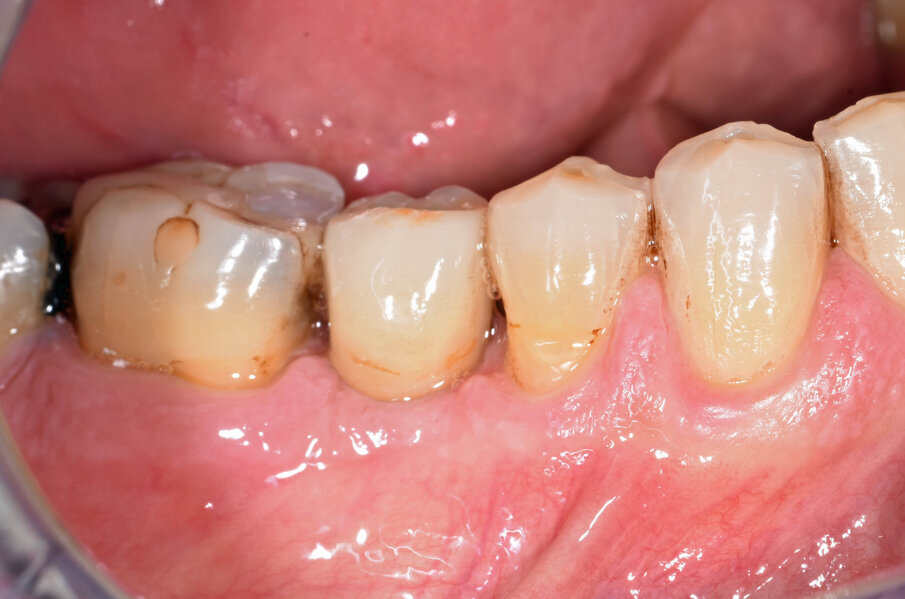

G. I. paziente di anni 50, si presenta alla nostra osservazione con una frattura longitudinale della radice dell’elemento 4.5 dovuta a infiltrazione cariosa della vecchia corona protesica. Questa situazione ha provocato nell’osso alveolare del paziente una grossa lesione che è andata ad interessare anche la corticale vestibolare. Per poter sostituire la radice con un impianto sarebbe necessario un intervento di chirurgia ossea rigenerativa ma un’alternativa meno invasiva è la rigenerazione del tessuto osseo ottenuta tramite l’estrusione forzata dell’elemento che rigenera osso durante la sua lenta migrazione grazie al legamento parodontale. In accordo con il paziente, dopo opportuna spiegazione dei benefici e dei tempi dell’approccio con estrusione ortodontica, si decide di procedere con questo iter evitando così l’intervento di rigenerativa.

In questo caso clinico la difficoltà consisteva nel fatto che si è resa necessaria l’estrazione della metà mesiale della radice fratturata e quindi nel far compiere al frammento radicolare rimasto un movimento diagonale per mezzo del quale la porzione distale rimasta con il legamento parodontale avrebbe permesso una corretta rigenerazione tissutale ossea come indicato in rosso nell’immagine radiografica.